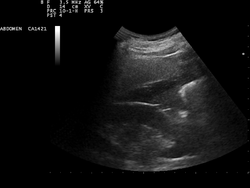

A normal ultrasonographic view of Morison's pouch. The bright line is the capsule of the kidney; there is no fluid present and hence no visible space.

Ultrasound of liver (left side of the image) and right kidney (right side of the image) and Morison's pouch, not containing fluid.- Abdominal CT, showing Morison's pouch as the dark margin surrounding the right kidney (at lower left corner of image).